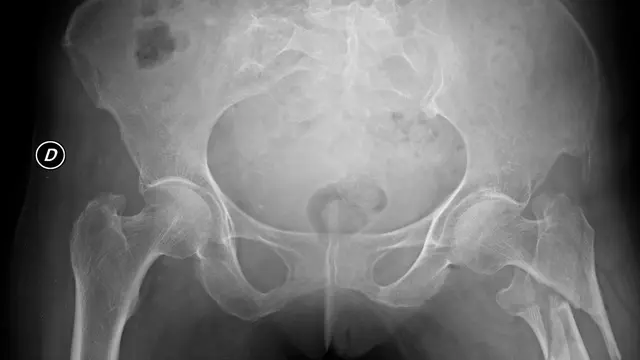

Fimela.com, Jakarta Hip arthroscopy atau pembedahan pinggul terdengar asing didengar publik Tanah Air. Sebab, di Indonesia memang minim pengetahuan mengetahui hal tersebut. Atas dasar itulah, dokter asal Malaysia, Prof dr Ruslan Nazaruddin Simanjutak memberikan workshop terkait hip arthroscopy di kawasan Tunjungan, Surabaya, Sabtu (4/3/23).

Dokter yang bekerja di Alty Orthopaedic Hospital, Kuala Lumpur, Malaysia menyebut kemungkinan banyaknya masyarakat Indonesia mengalami sakit pinggul. Namun di satu sisi, banyak dokter yang belum paham mengenai penyakit tersebut sehingga ada kesalahan diagnosa.

Untuk memastikan titik bedah tepat sasaran, biasanya dokter ortopedi mempelajari kasus pembedahan tulang belakang menggunakan kadaver atau mayat terlebih dahulu.

Lebih lanjut, Prof Ruslan mencatat hingga saat ini baru ada dua dokter Indonesia yang memiliki keterampilan dalam hal hip arthroscopy. "Satu di Jakarta, satu lagi di Bandung. Di Surabaya, baru kali ini workshop sama dokter Unair," katanya.

Hip arthroscopy bisa dialami siapa saja, dari umur 30-70 tahun. Namun kebanyakan, kasus ini dialami para atlet, seperti atlet sepak bola, lari, lompat dan badminton yang mengalami cidera.